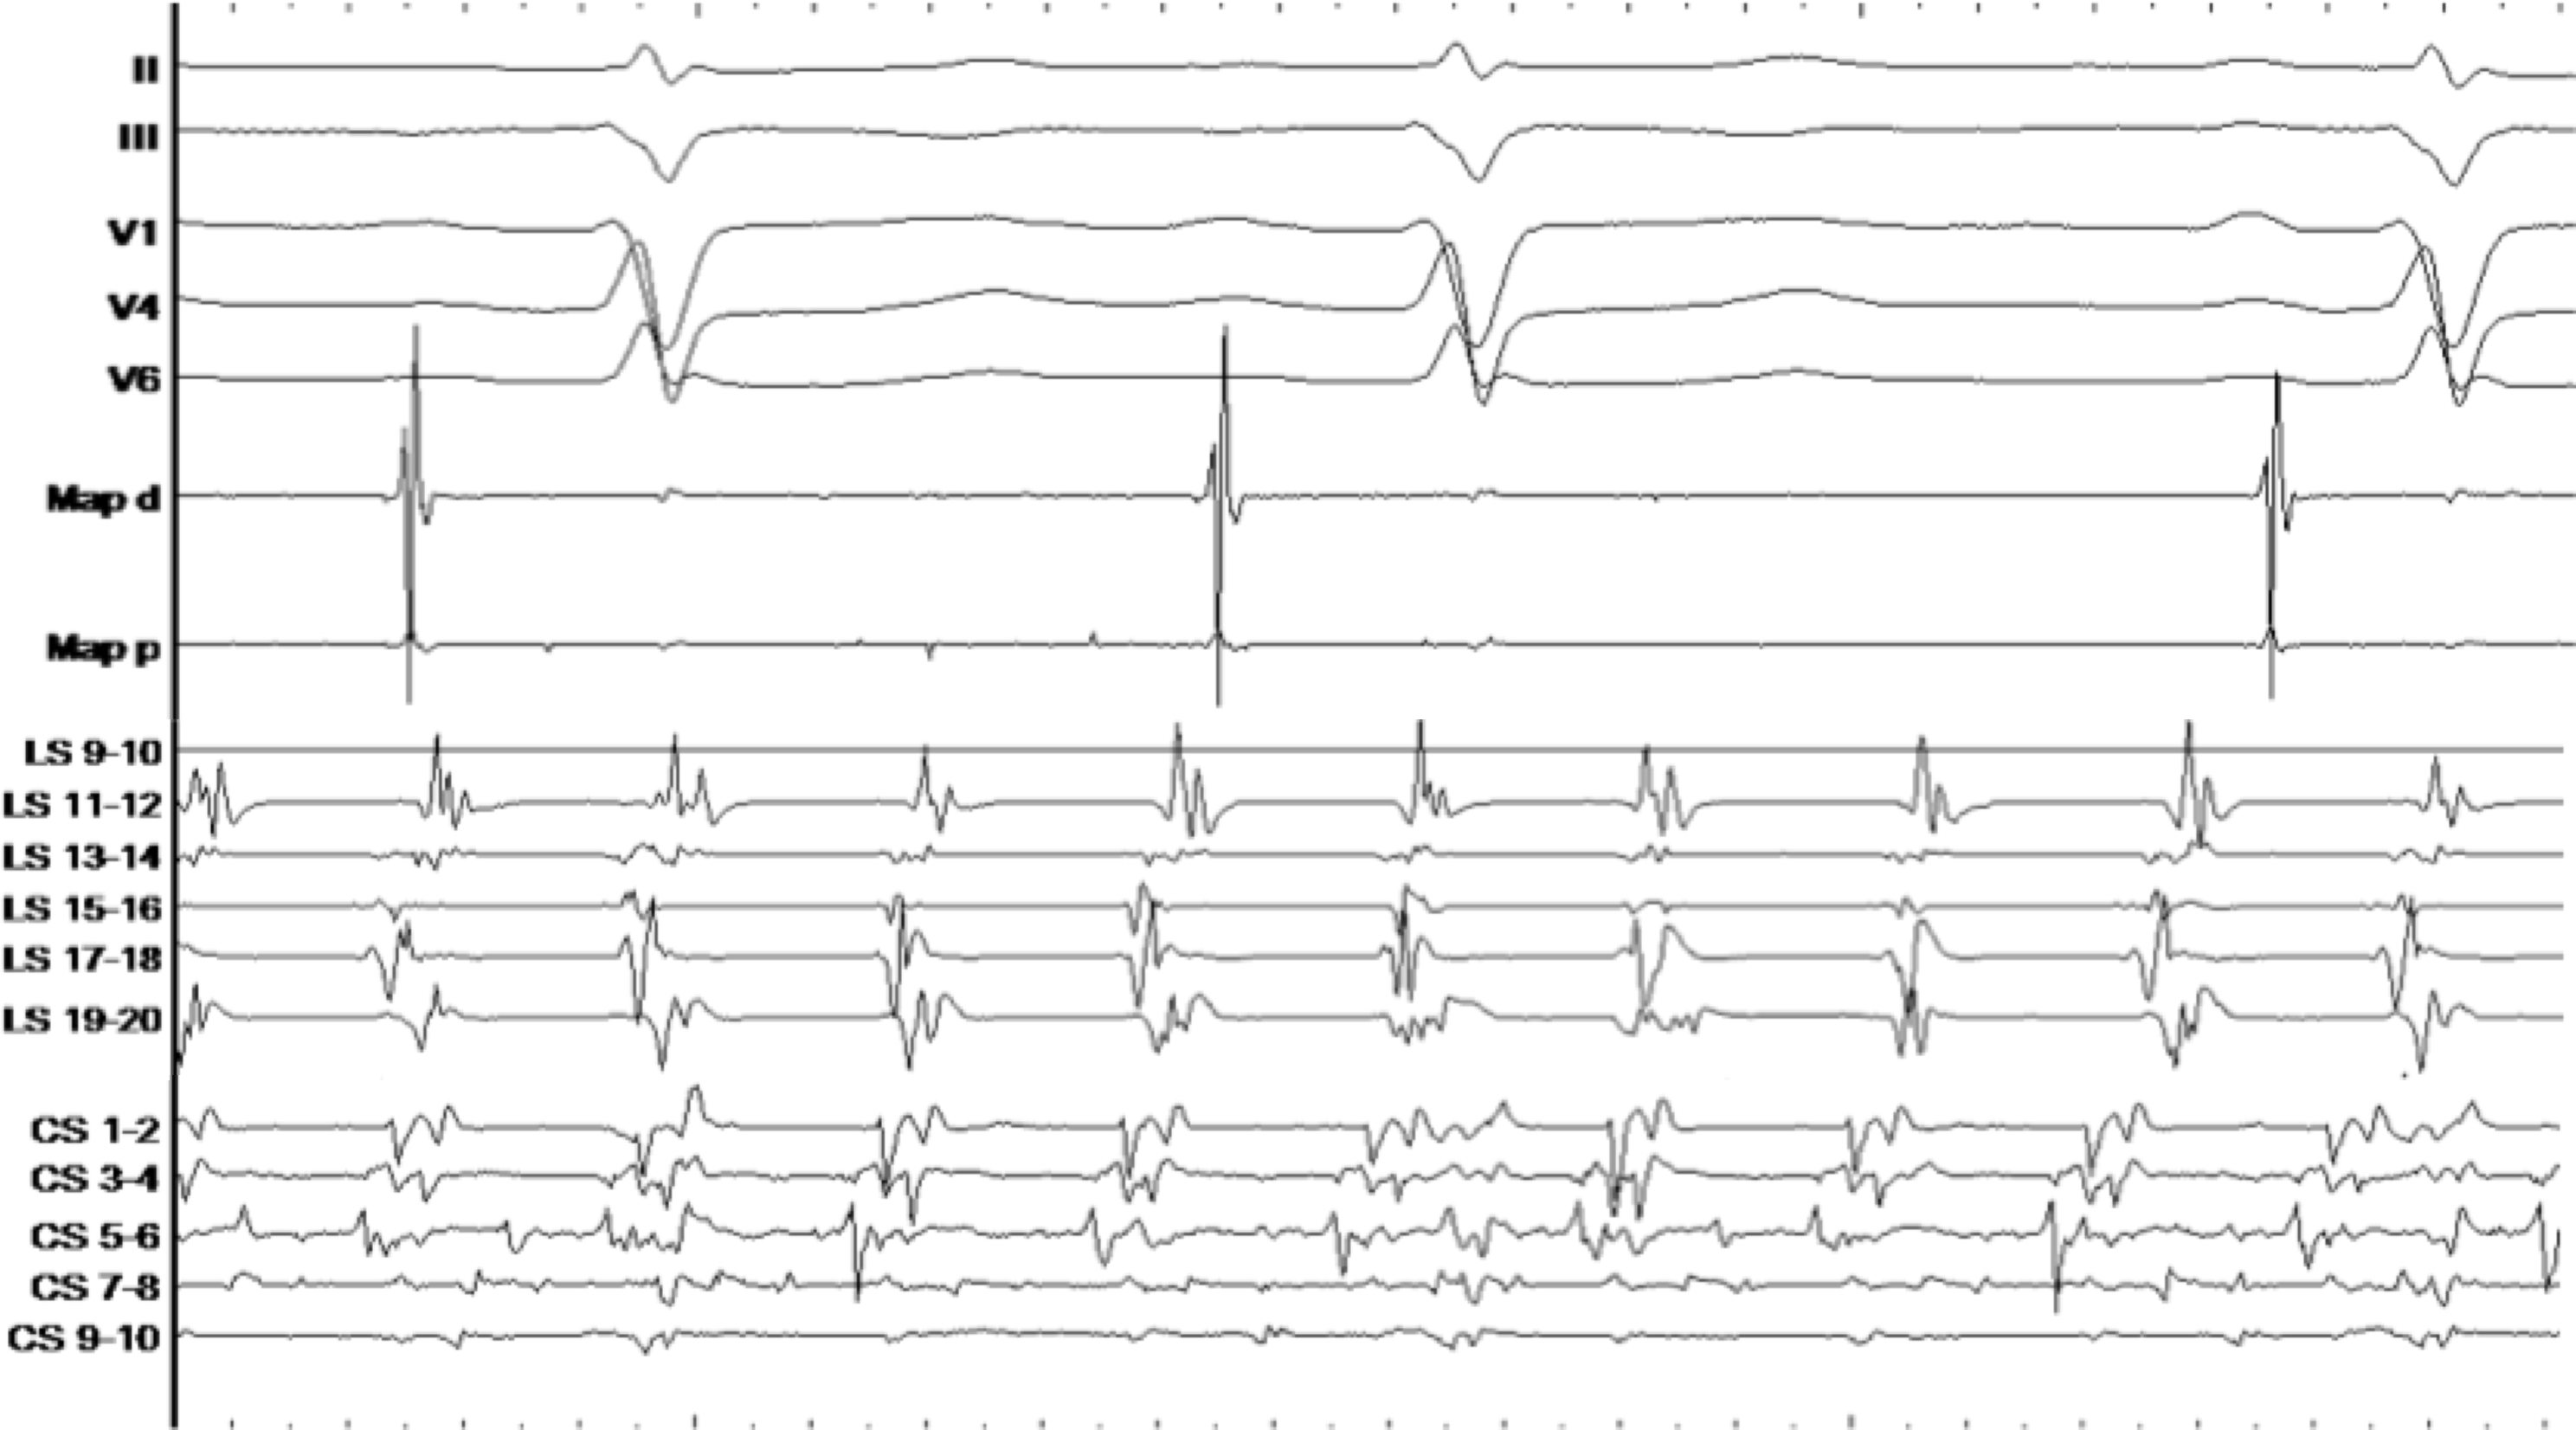

Abstract 65 Elektrische Isolation Des Linken Vorhofs Bei Einem Patienten Mit Paroxysmalem Vorhofflimmern Und Multiplen Katheterablationen